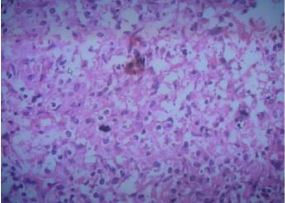

All patients were tested for Brucella bacteriology and drug sensitivity during febrile period after admission. Blood culture was positive in 12 cases (17.14%), and bone marrow culture was performed in 58 cases with negative blood culture, of which 23 cases were positive (39.66%). In group B, 22 patients (52.38%) were positive for intrafocal inflammatory granuloma or abscess sampling culture during operation, Under the microscope of Brucella G staining oil, the morphology is small Gram-negative bacillus, without buds, capsule and flagella, and Jim staining is purple (Figure 1),

Figure 1 Bacterial culture of Brucella was positive. The morphology of Brucella G stained oil microscope was Gram-negative small coccobacillus.

It was sensitive to doxycycline, rifampicin, streptomycin, penicillin and sulfamemethylisooxazole, but not to isoniazid, ethambutol, pyrazinamide and amikacin. The patients in this group were negative for rheumatoid factor, bone-derived alkaline phosphatase, human tissue-identical antigen, and antihemolytic streptococcin O.